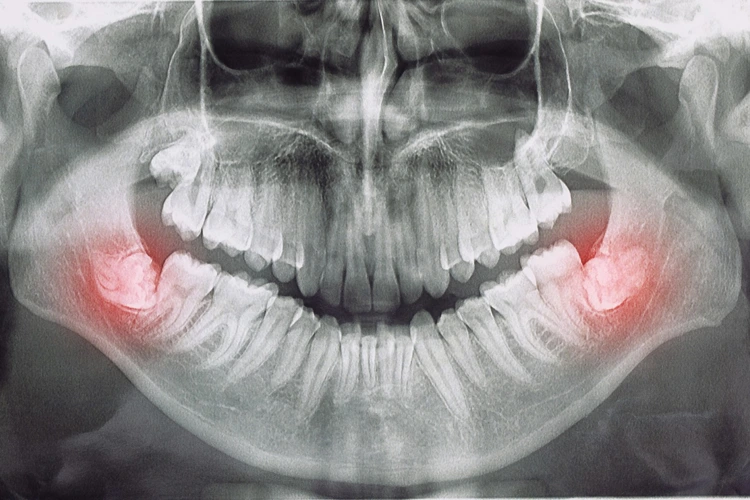

X-Ray image of 2 wisdom tooth causing problems to patient's dental well-being.

Wisdom tooth extraction is a common dental procedure, performed to remove one or more of the four third molars located at the back of the mouth. While some individuals never experience issues with their wisdom teeth, others develop problems such as impaction or infection that require removal.

Symptoms can include discomfort and pain, and in more serious cases, may involve infections, cyst formation, or damage to neighbouring teeth.